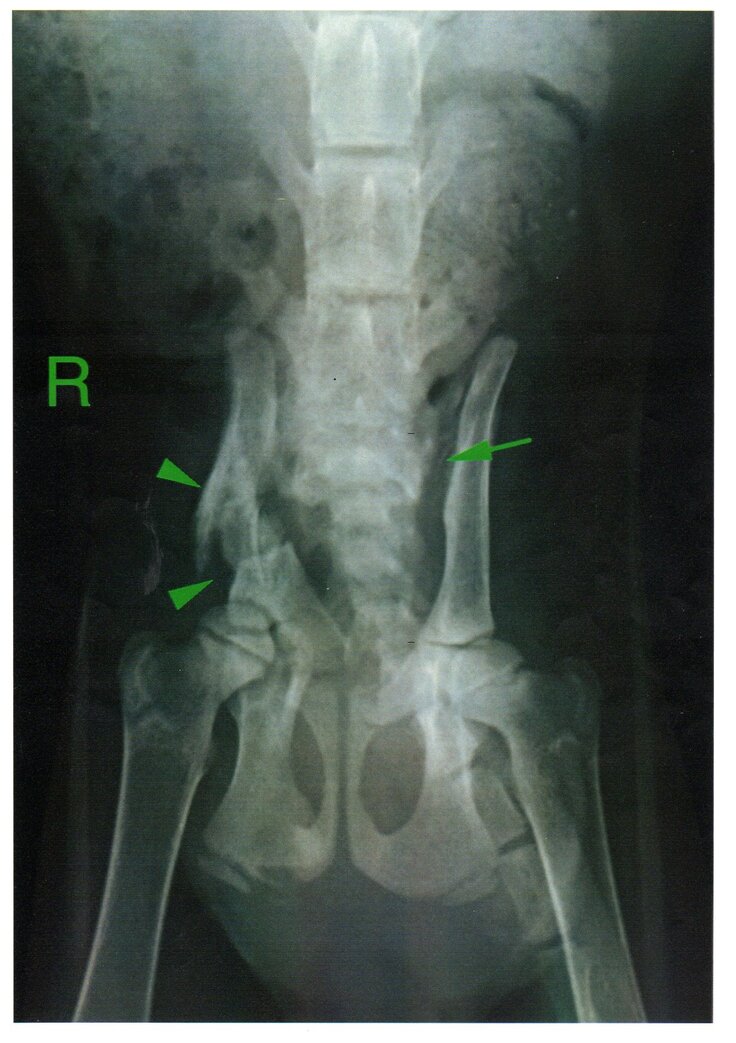

先生からご説明いただいた内容と写真、診断書、および診療明細書

(骨折箇所 骨盤骨折、右腸骨体粉砕骨折、右恥骨骨折、左側仙腸関節脱臼)

娘と娘の友達が国道で交通事故にあった子猫を保護したので、すぐ病院に連れて行き、足を怪我しているようなので、レントゲンを撮ってもらいました。すると、足だけではなく、事故の衝撃で骨盤の複雑骨折や、内臓の損傷が見られるとのこと、それを治すための手術が必要であることがわかりました。子猫が少しでも生活しやすいように手術をするため、みなさんのお力をお借りしたいです。